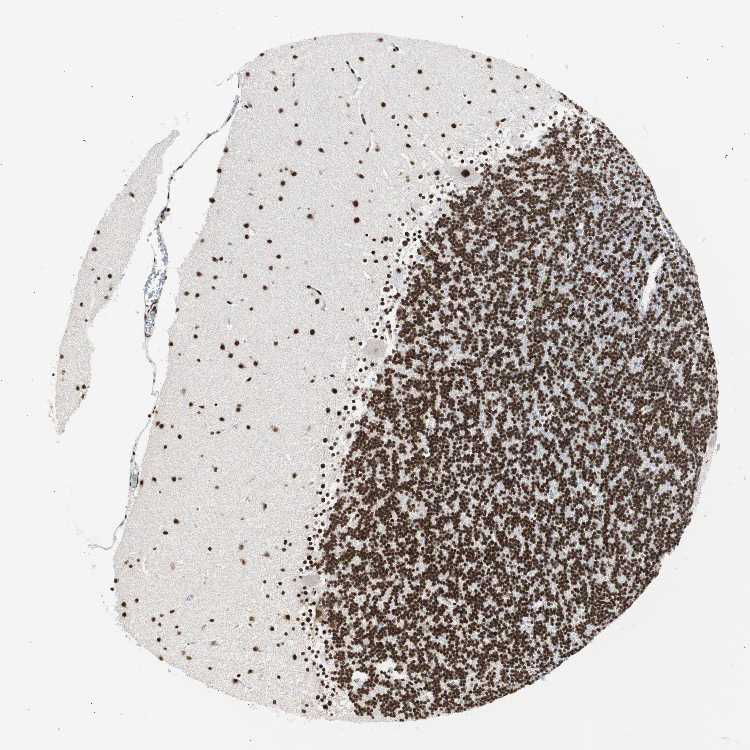

CEREBELLUM - Antibody stainingi

Antibody staining in the annotated cell types in the current human tissue is reported as not detected, low, medium, or high, based on conventional immunohistochemistry profiling in selected tissues. This score is based on the combination of the staining intensity and fraction of stained cells.

Each image is clickable and will lead to virtual microscopy that enables deeper exploration of all samples and also displays staining intensity scores, fraction scores and subcellular localization as well as patient and tissue information for each sample.

Antibody HPA006214Antibody CAB005315Antibody CAB017522

Purkinje cells HighHighHigh

Cells in granular layer HighHighMedium

Cells in molecular layer HighHighHigh